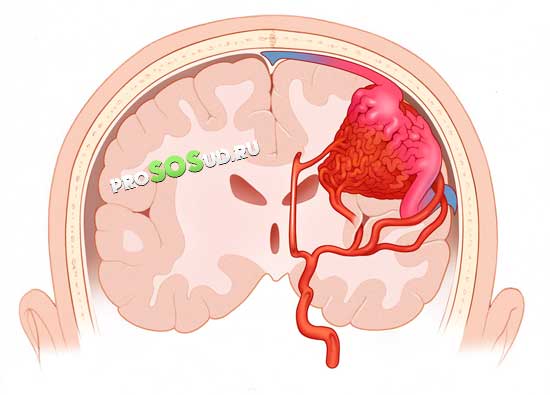

Следует отметить, что именно сосудистые аномалии становятся причиной возникновения ангиом в 95% случаев. Опухоли, расположенные на поверхности кожи, не представляют серьезной угрозы. Однако гораздо более опасны образования, затрагивающие мозг.

Поскольку заболевание связано с риском кровоизлияний, его необходимо быстро диагностировать и лечить. В противном случае могут возникнуть серьезные последствия, такие как инсульты, нарушения мозговой деятельности и эпилептические припадки.

Наиболее опасной считается венозная ангиома головного мозга, так как вероятность летального исхода в этом случае особенно высока. Кавернозный тип ангиомы может вызывать различные сосудистые патологии.

Каверны, представляющие собой сосудистые полости, являются основой этой серьезной патологии. Кавернозная ангиома головного мозга — это крайне опасное заболевание. Стенки каверномы разделены тонкими и не очень прочными перегородками. В случае разрыва образования может произойти мозговое кровоизлияние, что в свою очередь может привести к летальному исходу.

Венозная ангиома

Данная патология создает постоянное давление на мозг и часто сопровождается кровоизлияниями. Уровень смертности значительно выше, чем при каверномах.